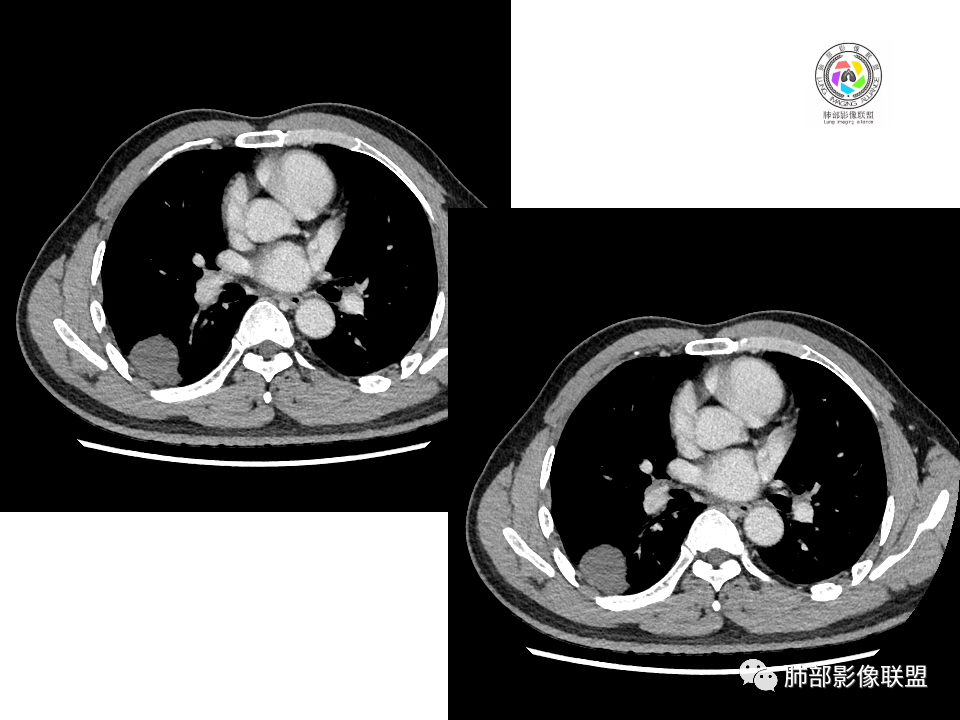

中年男性,体检发现占位。右肺下叶背段胸膜下肿块,周围晕征,有小分叶,与支气管、肺内血管关系不清,形似山丘,重建可见肿块呈D字形凸向肺部。似跨斜裂,似有小凸起与肋下缘相连,增强似有轻微均匀强化。右肺下叶外基底段小结节,位于血管周围,部分边缘平直,轻微均匀强化。考虑二元:一、右下叶背段肿块为肺外病变,神经鞘瘤?SFT?鉴别小细胞癌、隐球菌病;二、右下叶外基底段结节考虑为良性结节、炎性肉芽肿?

大小两个结节,形态类似,强化一致,都是乏血供病变,也无明显坏死,不符合炎性肉芽肿强化特点了,大结节膨隆明显,有局部突出,有长期吸烟史,所以考虑神经内分泌肿瘤可能(小细胞>不典型类癌),另外不典型错构瘤需要鉴别。最终还是需要穿刺病理确定。

血管也是稍推移,在边缘,病灶密度均匀,边缘稍收缩;均匀强化;

这两个病灶的密度、强化、形态、边缘、与血管的关系类似;还是一元论吧。

②恶性:间叶来源肿瘤,间叶来源的两个病灶的罕见;癌一般还是与支气管关系密切,有如果考虑癌,自然是小细胞癌(山丘征);但是因为没有看到支气管具体情况,不太踏实。

2.右肺下叶背段胸膜下块影,边界清楚光整,上下极见磨玻璃晕,未见明显分叶毛刺和棘状突起,未见胸膜凹陷或胸壁侵入。密度均匀,轻度不均匀强化。未见支气管进入。

4.右肺下叶基底段支气管血管束旁小结节影,边界清楚,强化不明显。注意,这结节在“遥远的”基底段。

注意,基底段支气管血管束旁的小结节影,即便是淋巴结,也与背段病灶引流途径不符。

4.良性占位绕不过去,如发生于该部位的孤立性纤维瘤等……